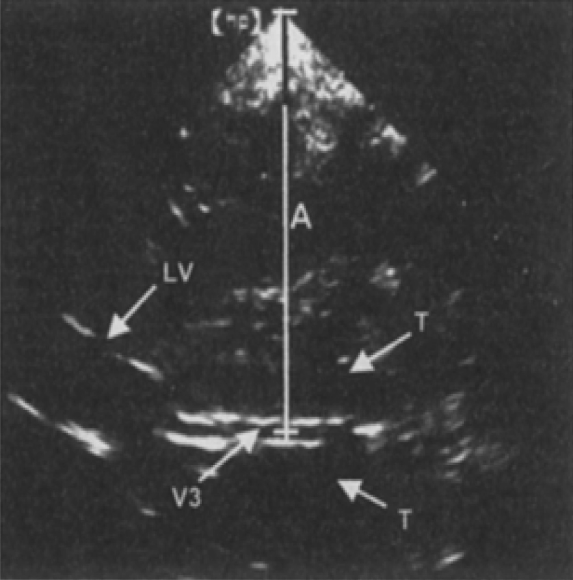

超声结构性评估定性监测 ICP 主要通过中线结构是否存在位移判断。可在图像中间观察到蝴蝶形的低回声的中脑脑干成像。将探头角度向间脑和脑室倾斜可以显示三脑室和侧脑室正面,可见到明显的超声波遇到室管膜正交平面形成的高回声线边界( 又称双轨征 ),即正常的颅脑中线位置[24]。根据双轨征到两侧颅骨的距离是否相等判断颅脑中线移位情况 ( 图 1-1)。